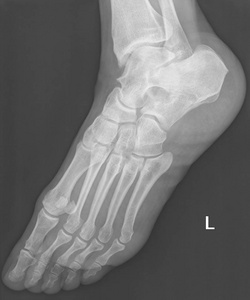

左足侧x光片

图片尺寸711x1200